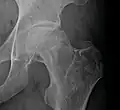

Radiography of avascular necrosis of left femoral head. Man of 45 years with AIDS.

Radiography of avascular necrosis of left femoral head. Man of 45 years with AIDS. -